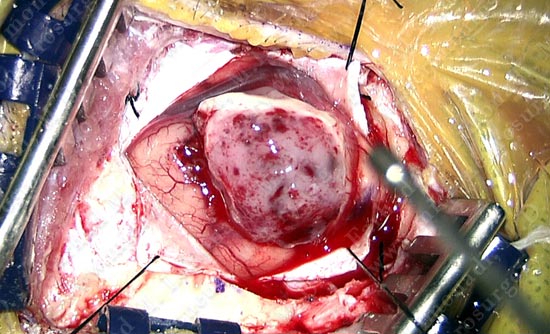

Surgical Procedure (view through the surgical microscope)

- She underwent right temporal craniotomy. Computer navigation was utilized to elevate a small bone flap of approximately 1 inch in diameter.

Dura is opened with temporal brain brought to view through a one inch window.

Tumor is removed from the right temporal lobe. It is almost as large as the surgical window.